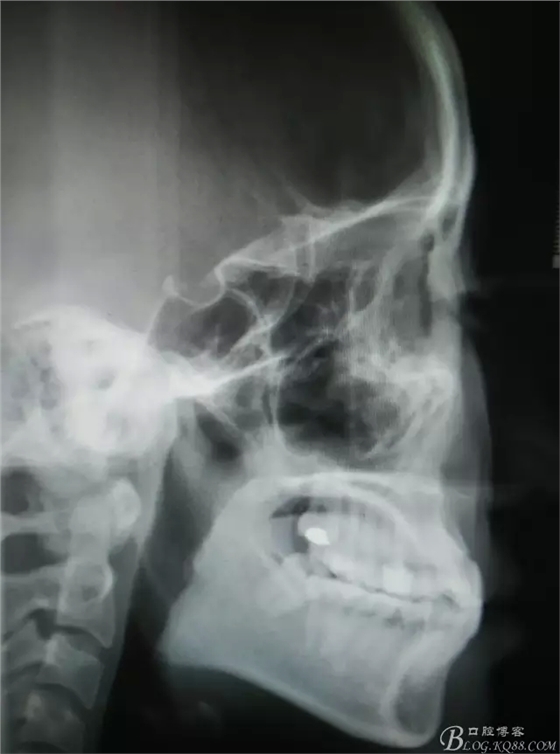

圖1.患者術前的全景片、側位片影像檢查:45牙根位于44與46之間,44與46鄰接緊密